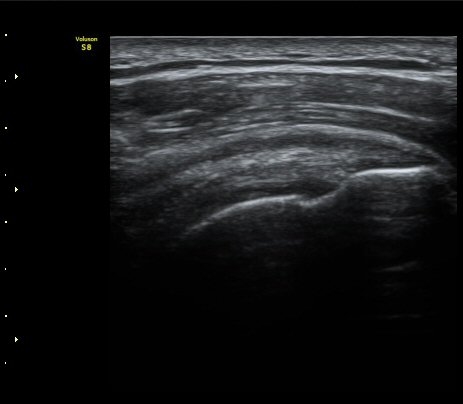

±Ø»ó°Ç³»Ãø Á¾´Ü¸é°Ë»ç¿¡¼­ ±Ø»ê°Ç ºÎÂøºÎÀÇ  ÀÛÀº ÆÄ¿­°ú Á¡¾×³¶ ºÎÁ¾ÀÌ °üÂûµÊ(±×¸² 2, 3).